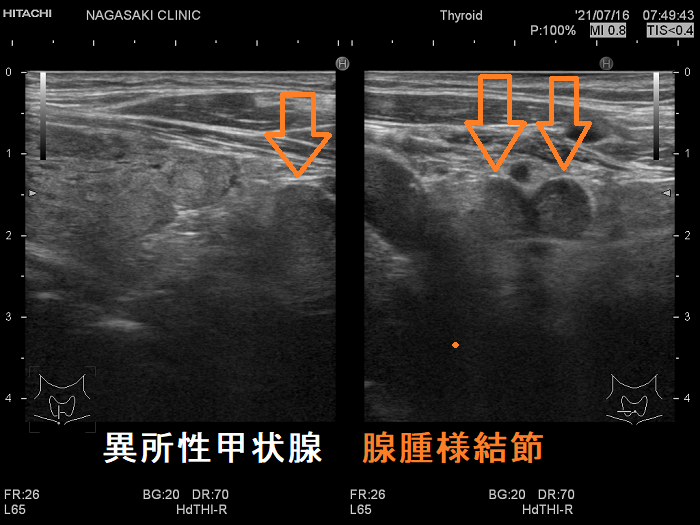

のう胞腺腫の下方にある頚部異所性甲状腺(非腫瘍)

左葉のう胞腺腫の下方に異所性甲状腺(非腫瘍)

左葉のう胞腺腫の下方にある頚部異所性甲状腺(非腫瘍):下極の副甲状腺と同じ位置。甲状腺本体と同様の組織です。

左葉のう胞腺腫の下方にある頚部異所性甲状腺(非腫瘍)

頚部異所性甲状腺(非腫瘍)の上にある左葉のう胞腺腫

ケース② 腺腫様甲状腺腫

腺腫様甲状腺腫の異所性甲状腺

腺腫様甲状腺腫の異所性甲状腺;甲状腺本体が腺腫様甲状腺腫なら、異所性甲状腺も腺腫様甲状腺腫。特徴的な2連構造を認めます。